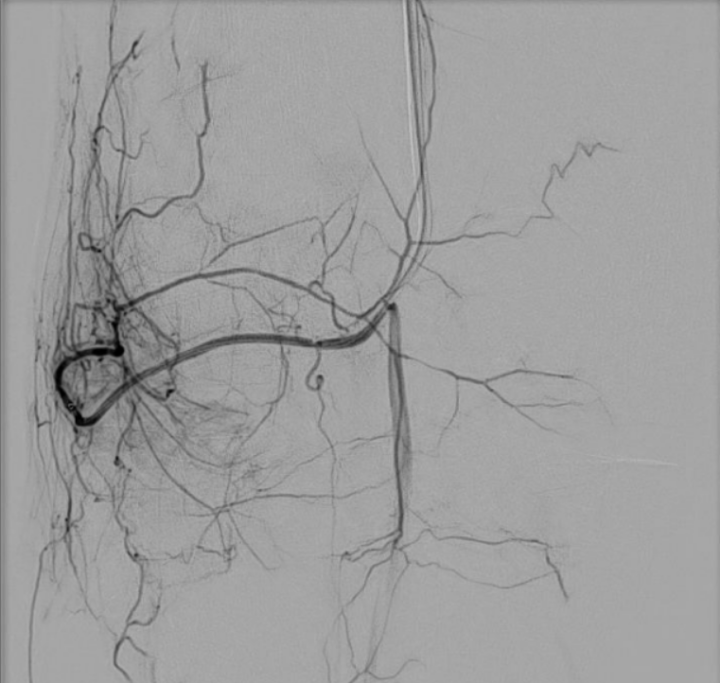

Das Verfahren beginnt mit einer kathetergestützten Zugangstechnik, bei der ein kleiner Katheter über eine Arterie eingeführt wird. Diese Katheter haben einen Durchmesser zwischen 1,5 und 2,5 mm und sind deshalb besonders gewebeschonend. Der Zugang der Behandlung erfolgt meist über die Leistenarterie oder einer Arterie am Arm (je nach dem Ziel der Behandlung). Die Katheter werden dann röntgengestützt bis zur behandlungsbedürftigen Region vorgeschoben. Dieses Verfahren ähnelt dem eines Herzkatheters. Nach Lokalisierung des Zielortes werden superselektiv die kleinsten Gefäße, welche für die Schmerzauslösung verantwortlich sind, mit einem Mikrokatheter (0,5 mm) sondiert. Es erfolgt dann Freisetzung der Mikroemboli, um die Blutzufuhr zu diesen spezifischen Bereichen zu blockieren. Diese Prozedur dauert zwischen 10-30 Minuten (je nach Erfahrung des Arztes und der Komplexität der Anatomie).